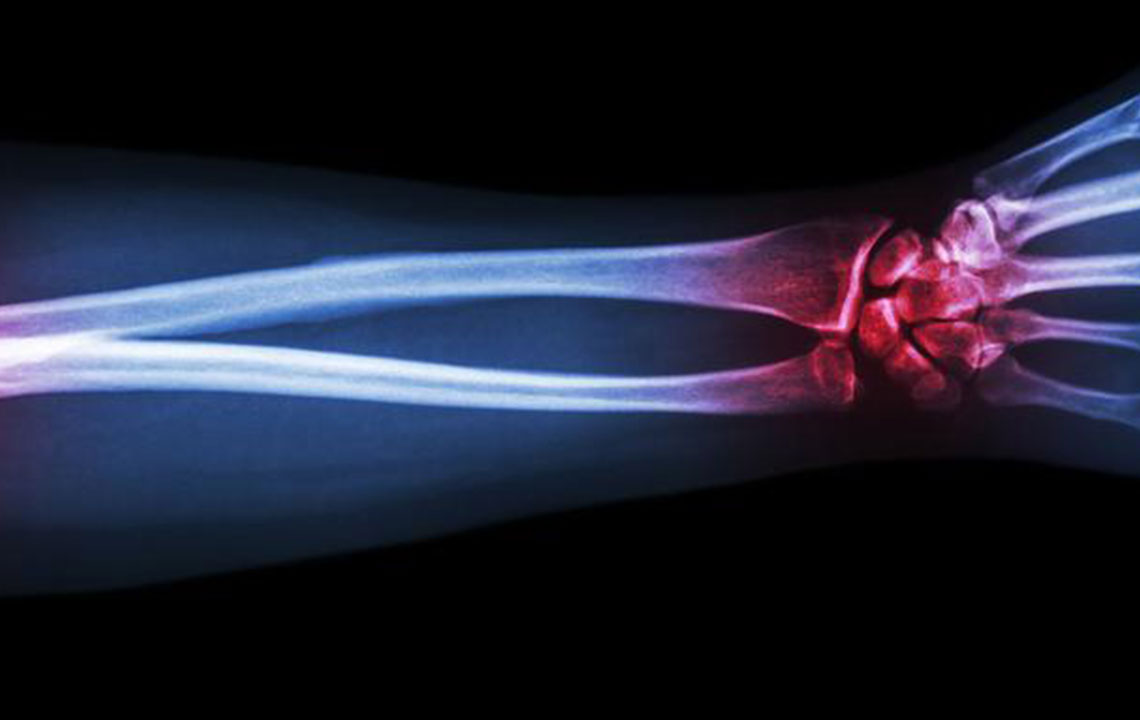

Gout is a type of arthritis that primarily attacks the joints and other body parts like the ears, wrists, knuckles, knee, ankles, and other small joints. It is often characterized by painful swelling, stiffness, and inflammation of these affected joints. The swelling and stiffness are mainly the results of excess levels of uric acid forming crystals in the joints.

The deposition of uric acid crystals in the joint causes inflammation and makes the movement of the joint agonizing. The elevated levels of uric acid in the system also causes the depositing of crystals in the kidney, which, in turn, leads to stone formation.